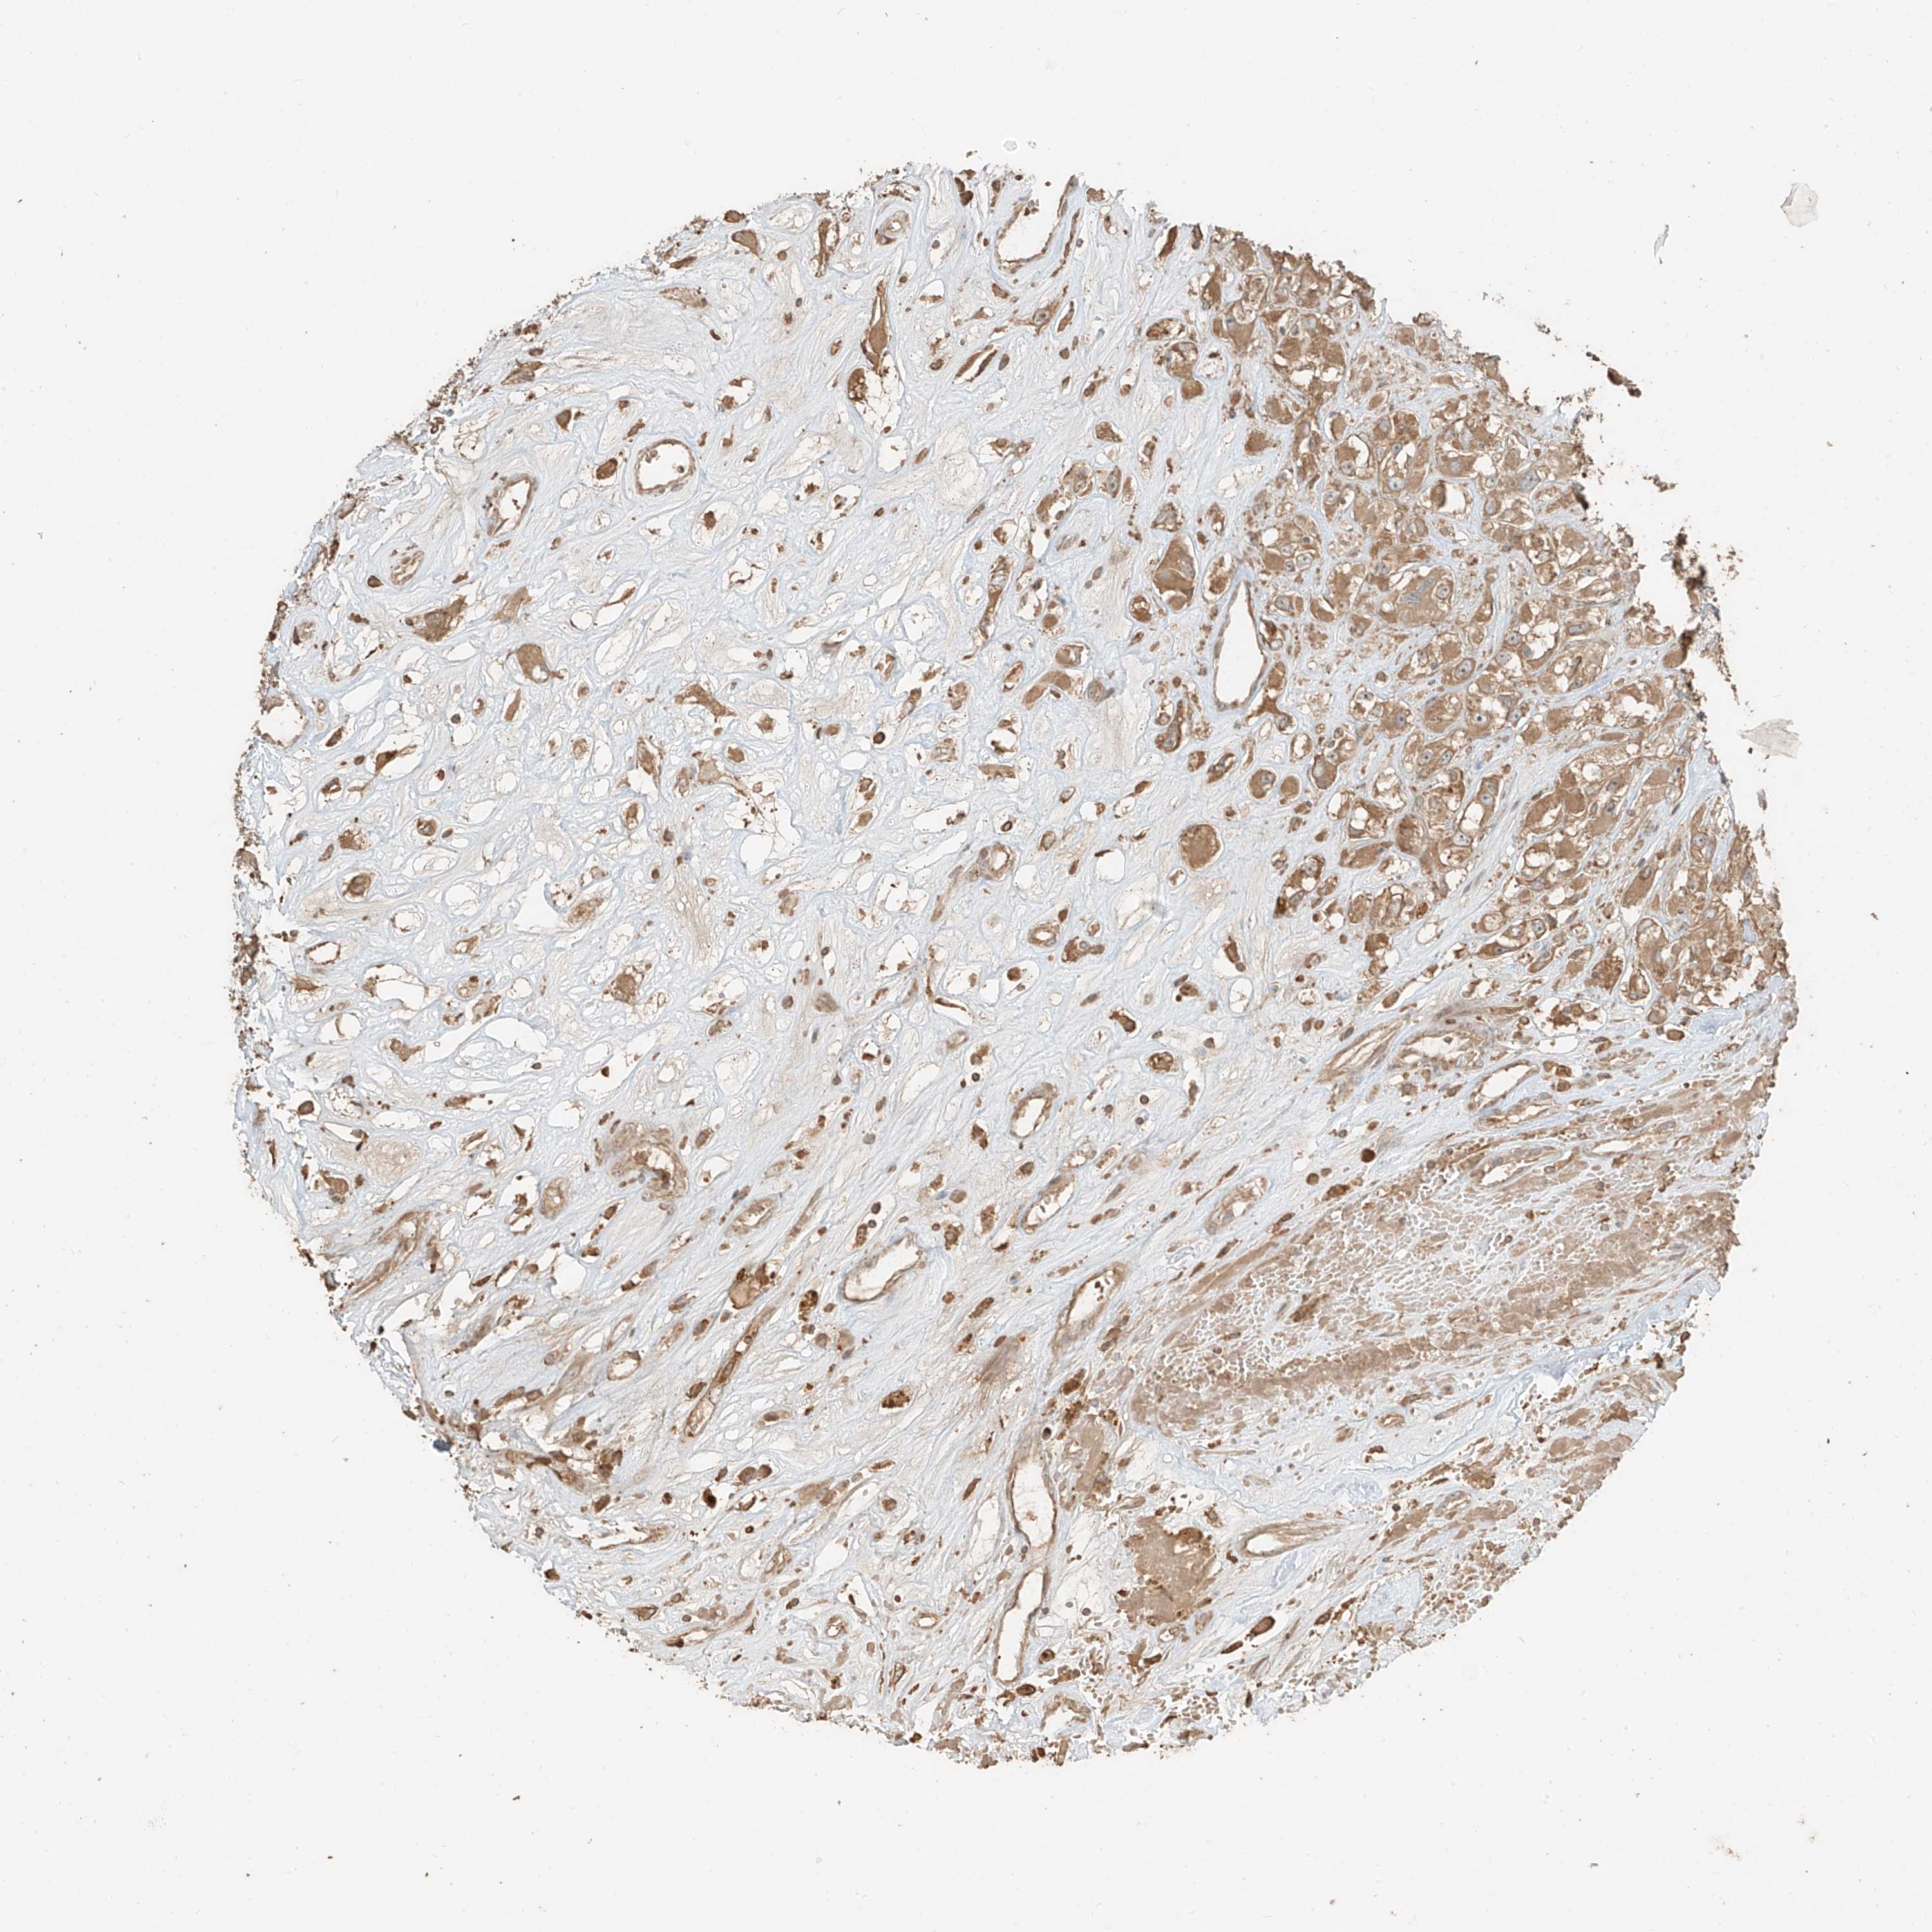

KIDNEY RENAL CLEAR CELL CARCINOMA (TCGA) - Interactive survival scatter ploti

The Survival Scatter plot shows the clinical status (i.e. dead or alive) for all individuals in the patient cohort, based on the same data that underlies the corresponding Kaplan-Meier plots. Patients that are alive at last time for follow-up are shown in blue and patients who have died during the study are shown in red.

The x-axis shows the expression levels (FPKM) of the investigated gene in the tumor tissue at the time of diagnosis. The y-axis shows the follow-up time after diagnosis (years). Both axes are complimented with kernel density curves demonstrating the data density over the axes. The top density plot shows the expression levels (FPKM) distribution among dead (red) and alive patients (blue). The right density plot shows the data density of the survived years of dead patients with high and low expression levels respectively, stratified using the cutoff indicated by the vertical dashed line through the Survival Scatter plot. This cutoff is automatically defined based on the FPKM cutoff that minimizes the p-score. The cutoff can be changed by dragging the vertical line or by entering a cutoff value in the square labeled "Current cut-off".

Under the Survival Scatter plot the p-score landscape (black curve; left axis) is shown together with dead median separation (red curve; right axis). Dead median separation is the difference in median mRNA expression between patients who have died with high and low expression, respectively. It is calculated as follows: median FPKM expression of dead patients with high expression - median FPKM expression of dead patients with low expression. This is intended to aid the user in visually exploring custom cutoffs and the associated p-scores and dead median separation.

Individual patient data is displayed and can be filtered by clicking on one or more of the category buttons on the top of the page. Categories describing expression level and patient information include: high, low, alive, dead, female, male and tumor stages. The scale of the x-axis can be toggled between linear and log-scale by clicking on the "x log" button. Mouse-over function shows TCGA ID, patient information and mRNA expression (FPKM) for each patient.

& Survival analysisi

Kaplan-Meier plots summarize results from analysis of correlation between mRNA expression level and patient survival. Patients were divided based on level of expression into one of the two groups "low" (under cut off) or "high" (over cut off). X-axis shows time for survival (years) and y-axis shows the probability of survival, where 1.0 corresponds to 100 percent.

RFTN2 is validated prognostic, high expression is favorable in Kidney Renal Clear Cell Carcinoma (TCGA)

Best expression cut offi

Based on the FPKM value of each gene, patients were classified into two groups and association between prognosis (survival) and gene expression (FPKM) was examined. The best expression cut-off refers the FPKM value that yields maximal difference with regard to survival between the two groups at the lowest log-rank P-value. Best expression cut-off was selected based on survival analysis .

When clicking on this number, the vertical dashed line indicating cut-off, the interactive survival plot, and the Kaplan-Meier curve will be adjusted to show results based on the best expression cut-off.

: 3.76

Average pTPM 3.4

Number of samples 521